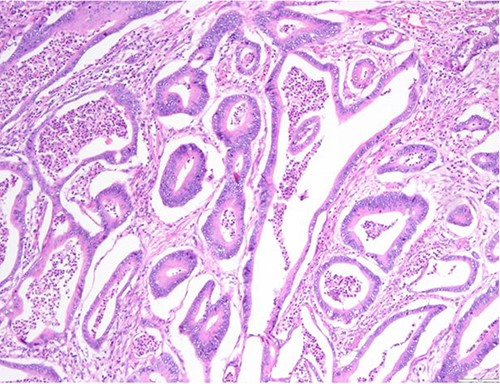

Surgical specimen: splenectomy; microscopy, HE; spleen parenchyma infiltrated by well-formed neoplastic glandular structures composed of cells with ‘pencillated’ and atypical nuclei, with nucleoli, apoptosis and mitotic figures, consistent with an intestinal origin (metastatic colorectal adenocarcinoma).

Surgical specimen: splenectomy; microscopy, HE; spleen parenchyma infiltrated by well-formed neoplastic glandular structures composed of cells with ‘pencillated’ and atypical nuclei, with nucleoli, apoptosis, and mitotic figures, consistent with an intestinal origin (metastatic colorectal adenocarcinoma).